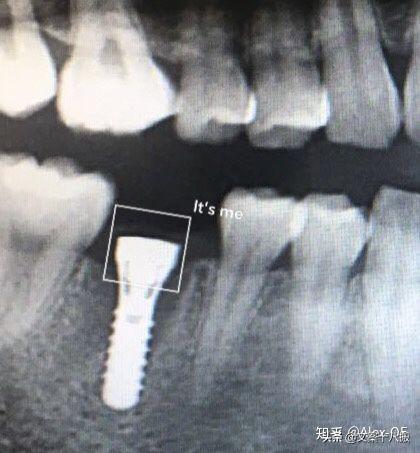

2018年7月6日,下午先拍了CT,很小劑量的輻射。主任方醫(yī)師說我的情況符合植牙條件,骨量也沒有問題,接下來安排了方案并開始手術,由方醫(yī)師操刀,整個手術由3個醫(yī)生共同完成。用消毒水漱口兩分鐘后,躺在那個椅子上,燈光刺眼,消毒棉花在口腔周圍一圈一圈得涂,鼻子上都涂了。身上蓋了做手術的綠布(這個布有名稱嗎?),只露出口腔。因為眼睛也在綠布底下,所以手術全程看不到醫(yī)生用過哪些工具,只能想象醫(yī)生在干什么,做了麻醉感覺不到切開牙齦,鉆孔的疼痛,但是植入牙體是有感覺的,畢竟那么大的東西硬生生的塞了進去,從醫(yī)生手肘的顫動知道這牙題塞進牙槽骨挺費勁的。術前忘記看時間了,估計今天整個過程開始到結束大概40分鐘,40分鐘內(nèi)還包括了十幾分鐘的醫(yī)生的清潔準備工作。沒有什么不適,不過醫(yī)生有一會兒手碰巧壓住鼻子上面的綠布了,就只能用嘴呼吸了。我也沒提醒醫(yī)生覺得很快就過去了,醫(yī)生說有任何不適可以隨時叫停。(因為在清潔的綠布底下,隨意抬手示意會造成污染,能不停就別停了,真的有不適吱聲就行)沒告訴他,大概憋了快一分鐘氣覺得種牙還沒有拔牙痛,只是長時間張著嘴比較難受,術后拍片醫(yī)生說果不錯,配了消炎藥和漱口水,臉貼著冰袋回去了,一周后拆線?,F(xiàn)在已經(jīng)過去8個小時了,麻醉藥也過了,有少量滲血,但疼痛感十分輕微。植牙回去以后,怕麻醉藥過去后疼,下午2點植入后敷冰袋到了晚上8點。那時候確實感覺到疼,不過是輕微而持續(xù)的疼,并且這種輕微的疼大概持續(xù)了四天,術后配的藥也差不多吃完,那之后就沒事了。